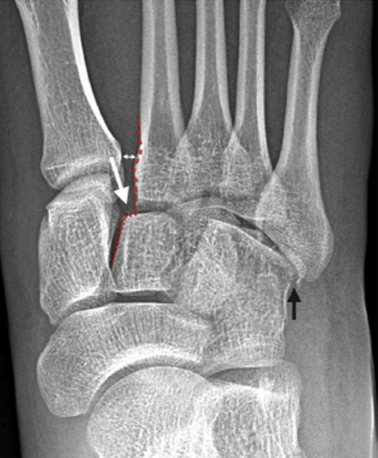

The "fleck-sign" (Fig. 10), an avulsion fracture of the base of the second metatarsal or medial cuneiform, is pathognomonic of a Lisfranc injury. (21) The radiograph shows a disruption of the C2-M2 alignment (red dotted line), a widening of M1-M2 (double-headed arrow), and a small fragment of bone ("fleck" sign) between M1-C2 (white arrow.) There is also a fracture of the cuboid (black arrow).